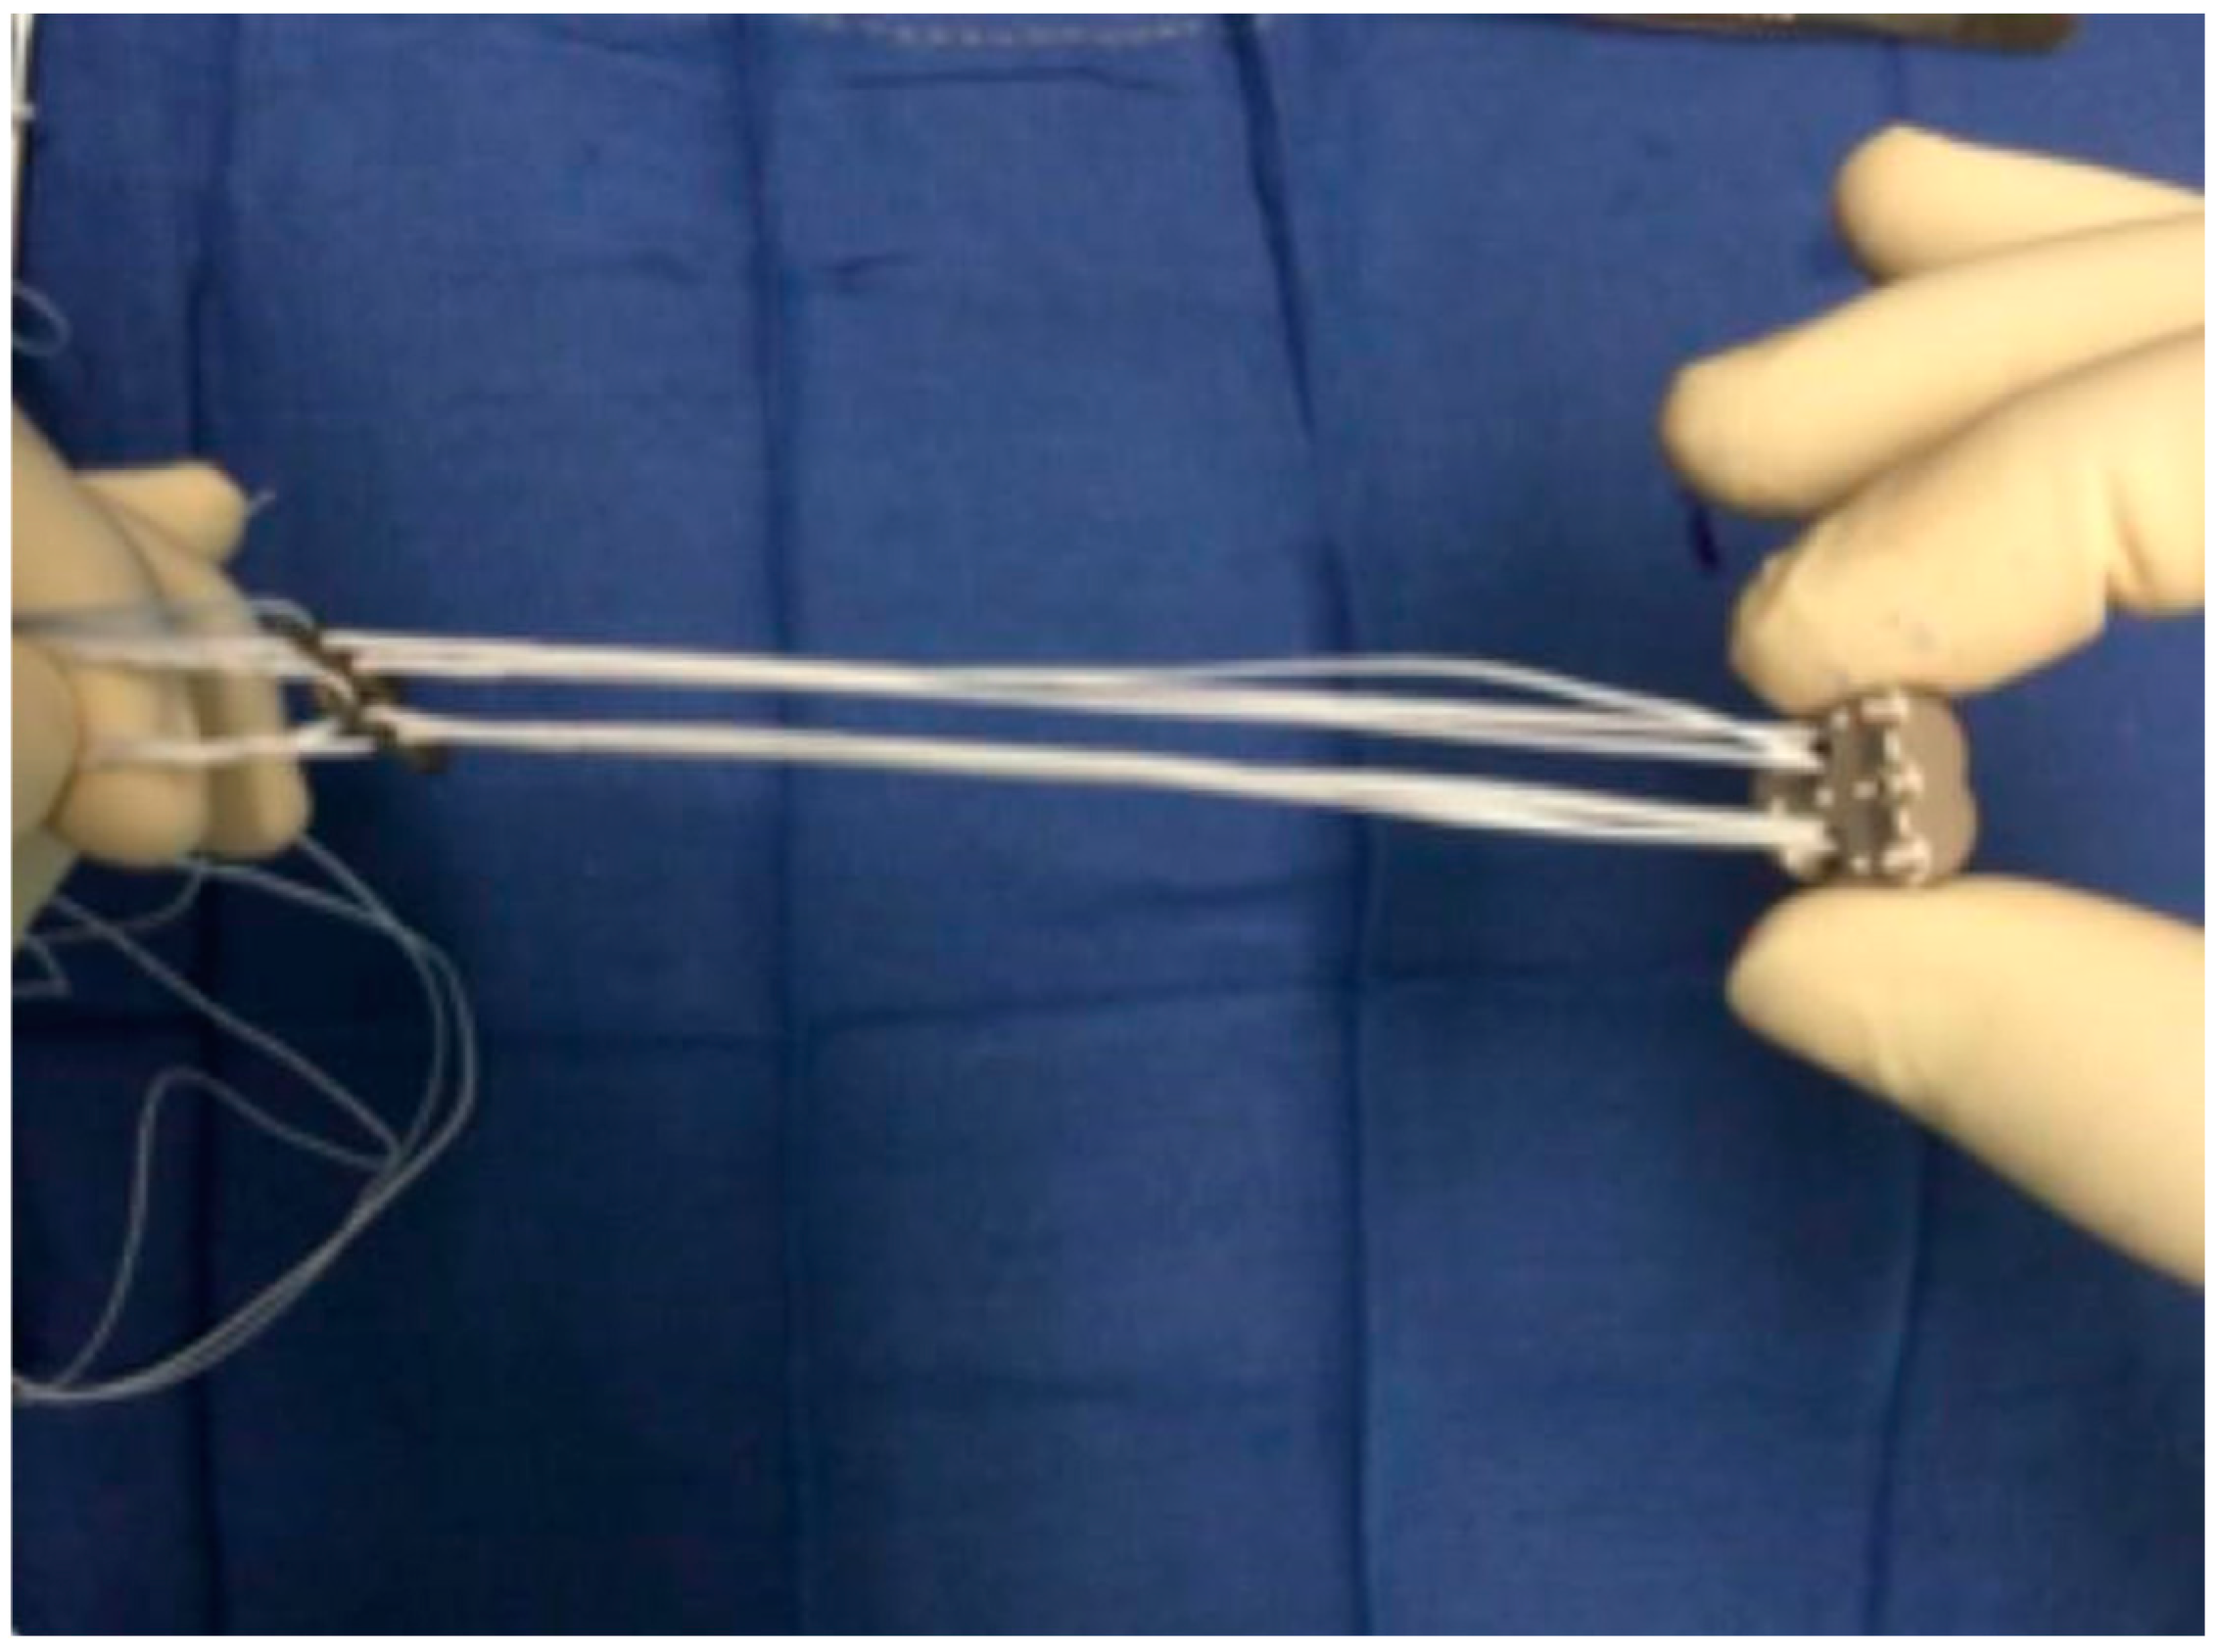

2.7.4. Step 4: Implant Positioning

2.7.5. Step 5: Bankart Repair